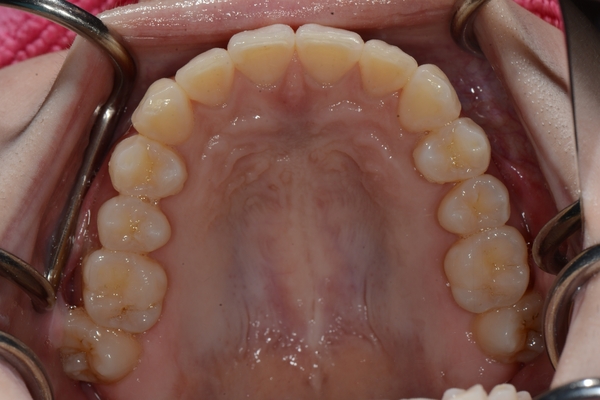

ガタガタとした歯並びや八重歯(叢生)CASE69